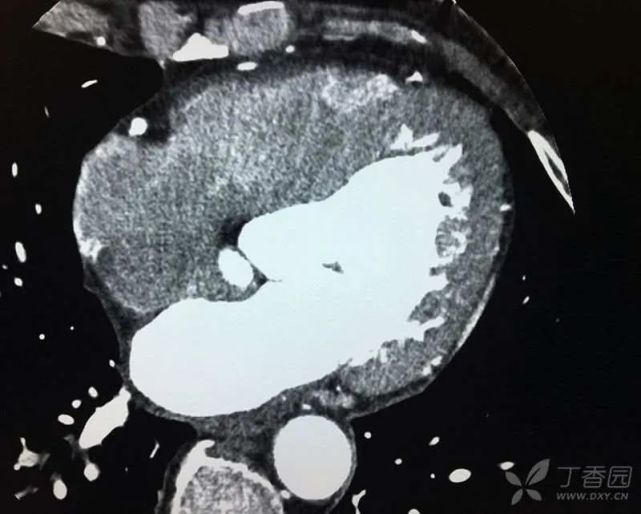

2012 年至 2015 年,患者 3 次因「活动后憋喘」入住我院心内科,诊断为:冠心病,慢性心功能不全(心功能II ~ II级)。住院期间查脑钠肽:9842 ~ 14835 pg/mL。心脏彩超结果显示:(1)室间隔、左室前壁运动幅度稍小;(2)左房增大,左室内径高界,二尖瓣少量返流;(3)主动脉稍增宽,主动脉瓣增厚伴少量返流;(4)左心功能测定:低界。冠脉 CTA:冠脉粥样硬化性改变,右冠远端、左冠前降支、对角支、回旋支轻度狭窄。心脏增大,左室为主(图3)。住院期间予地高辛、葛根素、螺内酯、氢氯噻嗪等对症治疗后。憋喘症状缓解,脑钠肽多可降至1000 pg/ml以下。

图片

(图 3 冠脉 CTA)